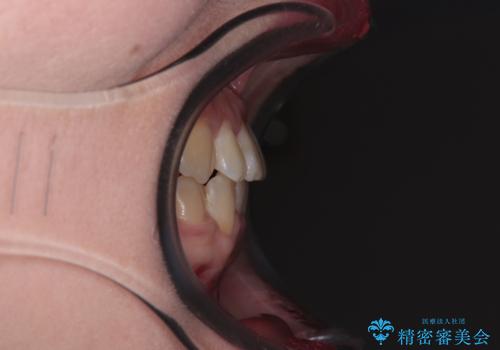

- 前歯の反対咬合を気にして来院された患者様です。

当院にて同様の咬み合わせを治療した方からのご紹介ということもあり、ご紹介者と同じワイヤー矯正で早めに治療を終えることを希望されました。

骨格的に下顎が前方に位置していましたが、歯列矯正で改善できると判断し、ワイヤー装置にて矯正治療を行うこととしました。

このような咬み合わせの方の多くは、舌の突出癖が強い傾向にあり、反対咬合改善後に開咬となってしまい、なかなか治療が終わらないことがあります。

こちらの患者様は、舌のトレーニングを治療開始前から徹底的に実践していただき、僅か8ヶ月という短期間で治療を終えることができました。